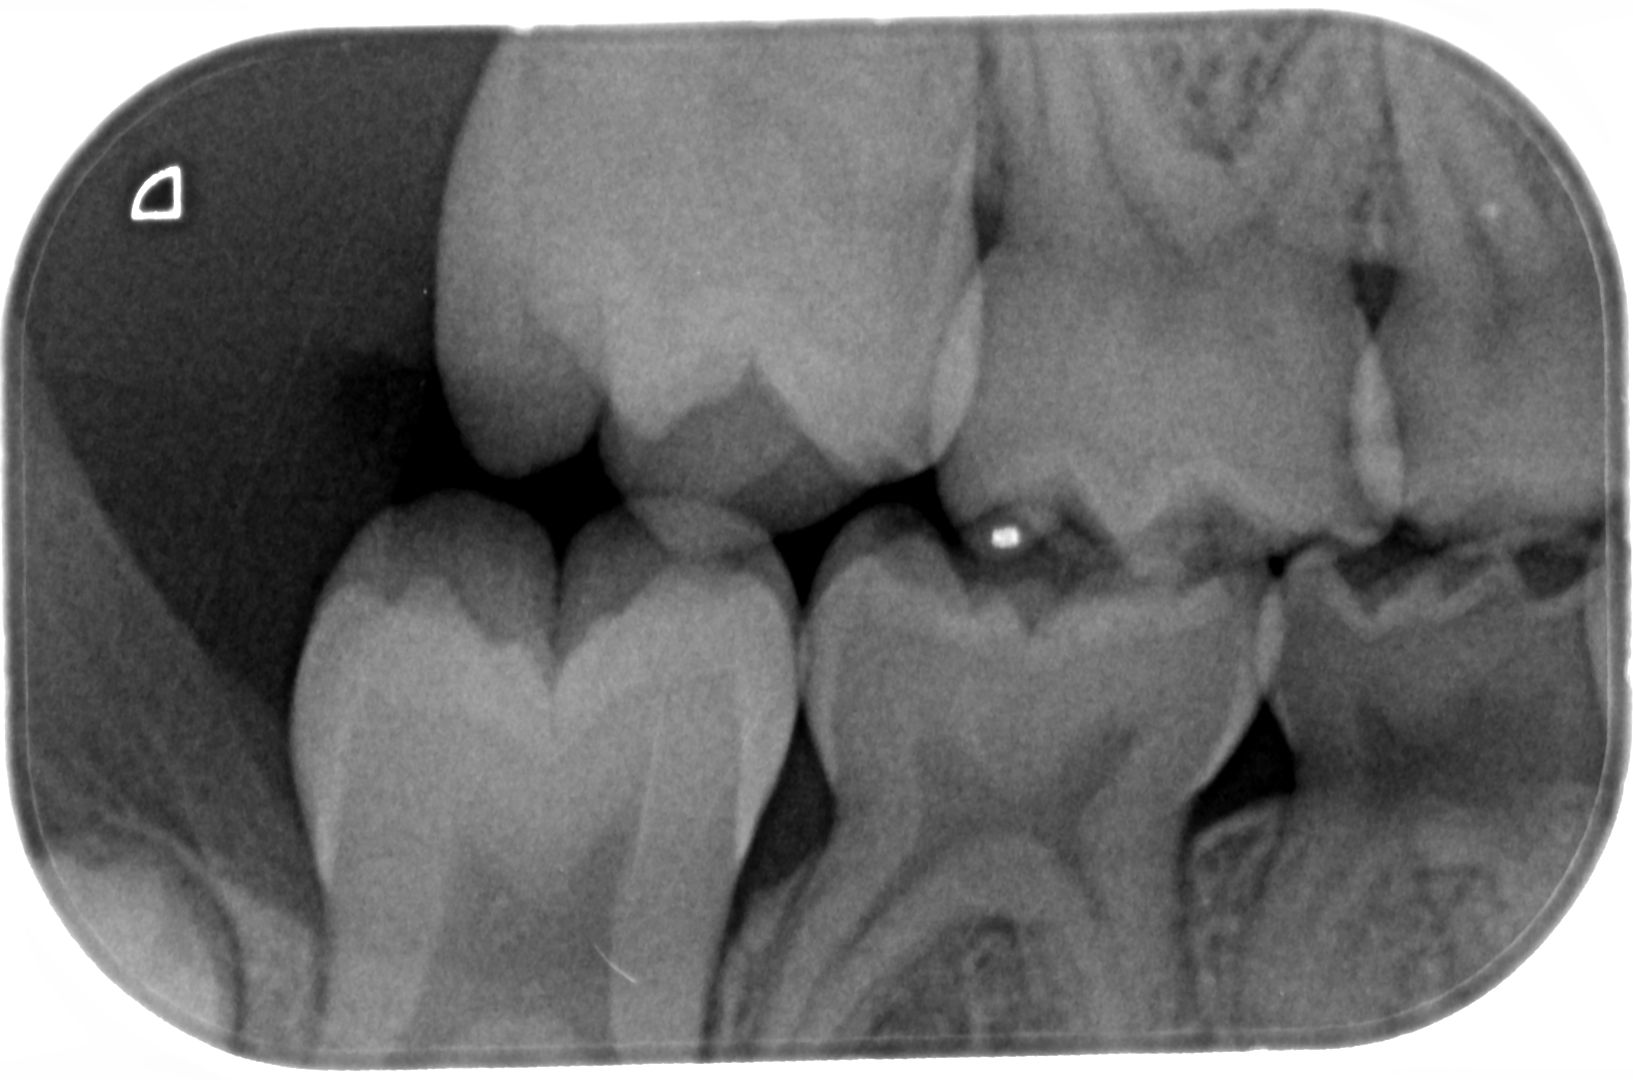

Bijgevoegd 2 XR-beelden van de melktand kiezen van onze dochter van 6. Bij een controle bij onze tandarts werden haar tanden visueel gaaf bevonden, maar wou men toch graag een foto maken. Hierop ziet de tandarts 6 gaatjes die ze in 3 sessies wil open maken en vullen. Uiteraard willen wij dat de gaatjes behandeld worden indien nodig. Echter doordat we het gevoel hebben dat er bij elk van ons steeds meerdere problemen gevonden worden waar we geen hinder van ondervinden, zou ik graag een tweede opinie vragen. Omdat ik zelf de beelden niet kan interpreteren, mijn vraag dus of er effectief 6 gaatjes te zien zijn en of het vullen hiervan aanbevolen is. Alvast bedankt voor uw hulp!

De XR beelden

Ik zie mogelijk een gaatje in de 55 en 54. Mogelijk omdat er een overprojectie is. Maar dusdanig klein dat ik zou afwachten tot uw dochter wat ouder is. Na een jaar een vergelijking foto. Maar ik zie geen zes op deze foto's.